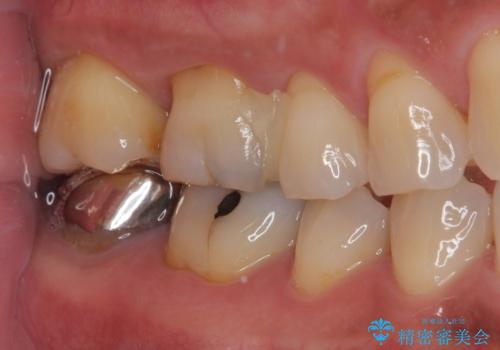

歯と歯茎の間に圧排糸と言われる糸を入れてシリコーン印象材にて型どりをしました。

ラバーダム防湿を行い、セラミックの接着をすることで、唾液や血液などの接着阻害因子を排除することができます。